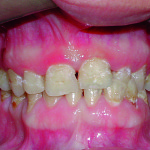

Ruolo dell’odontoiatra nella gestione di pazienti affetti da disturbi del comportamento alimentare

Dentist role in the management of patients affected by eating behaviour disorders

Obiettivo dell’articolo è analizzare le conseguenze sulla salute orale dei disturbi del comportamento...